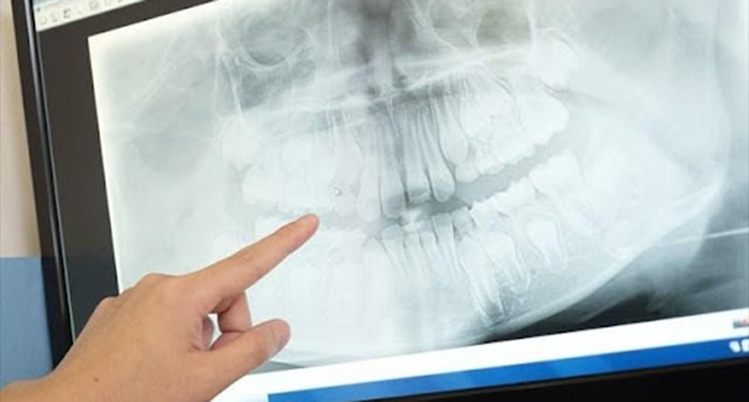

5.エックス線検査

レントゲン写真を撮って、骨の状態を調べます。前回、または次回と比較し、進行状態や進行速度を判断します。

歯ぐきの炎症を治すことは比較的簡単ですが、一度失った骨を元に戻すことは非常に困難です。悪化を防ぐためには、歯周病治療が欠かせません。

レントゲン画像を指さしている様子の写真